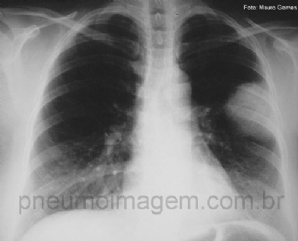

CASO CLÍNICO #23

Homem, 46 anos, apresenta-se com tosse seca há 3 semanas acompanhada por dispneia leve aos esforços. Nega febre e perda de peso. Tabagista por 20 anos/maço. Observe atentamente a radiografia de tórax, faça suas hipóteses diagnósticas e deixe seus comentários. ...